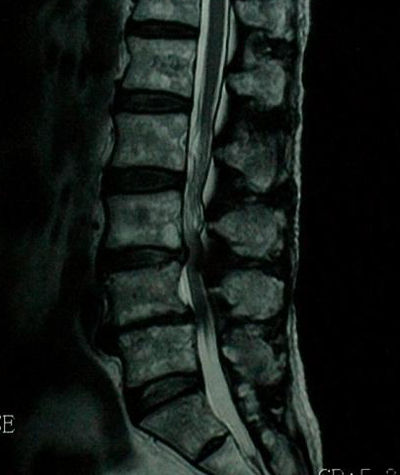

脊柱管狭窄症 Mri : 断面の脊柱管腔は純粋に客観的な評価となり,クモ膜 下腔の狭小化と術前の脊柱管狭窄症による症状の相関 表1 各椎間・撮影方法での脊柱管前後径比 l1/2椎間 l2/3椎間 l3/4椎間 腰椎mri 0.8660.830.679